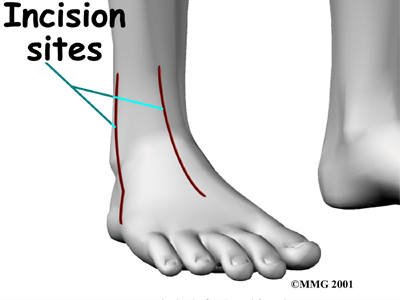

The Operation